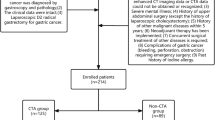

This study included 100 consecutive patients undergoing multidetector-row computed tomography (MDCT) between April 2009 and October 2010 before gastric surgery. The patient population consisted of 71 men and 29 women from 26 to 86 years of age (median age, 67 years). Ninety-eight patients had gastric cancer and 2 had gastric gastrointestinal stromal tumors.